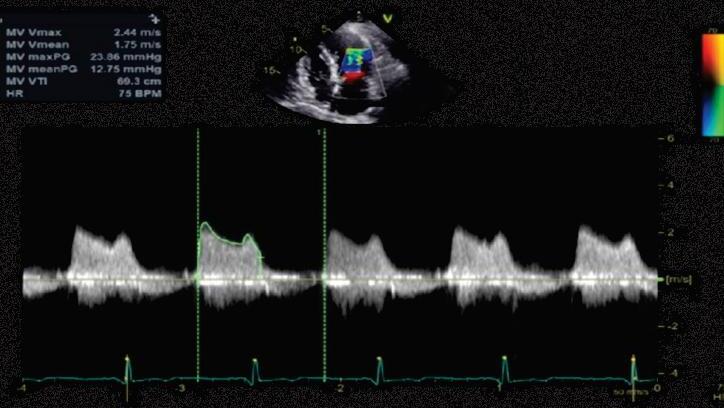

Coloque o paciente monitorado em uma maca, sentado ou recostado com inclinação de 45º; oriente que ele sopre uma seringa de 10mL pelo lado contrário ao do êmbolo, tentando empurrá-lo

Paciente do sexo feminino, de 53 anos de idade, em classe funcional II da New York Heart Association (CF-II NYHA), sem outras queixas no momento, apresenta: exame físico: pressão arterial (PA) = 126 × 70mmHg; frequência cardíaca (FC) = 64bpm; ausculta pulmonar sem alterações; ausculta cardíaca com ritmo cardíaco regular, B1 hiperfonética,

sopro regurgitativo mitral 2+/6+, ruflar diastólico 2+/6+, com estalido de abertura e reforço présistólico (Figura 6.1).

30. (Título de Especialista em Cardiologia) Jovem com queixa de fadiga e dispneia. Ao exame, apresenta bom estado geral e pulsos normais. À ausculta: primeira bulha hiperfonética, sopro diastólico em ruflar com reforço pré-sistólico. Ao eletrocardiograma: ritmo cardíaco regular, sinusal, eixo desviado para a direita e sobrecarga atrial esquerda (Figura 6.30A). Foi feito ecocardiograma (Figura 6.30B):

1. Resposta A

Essa questão é excelente para se exercitar a abordagem ao paciente que tem estenose mitral. Para tanto, vamos seguindo o passo a passo proposto pela Diretriz Brasileira de Valvopatias e complementando com conhecimentos que são essenciais para todo cardiologista que lida com pacientes valvopatas, especificamente os portadores de estenose mitral reumática. Primeiramente, vamos observar a Figura 6.1; em seguida, aplicaremos os conceitos.

 Passo 1: a questão descreve um paciente com quadro clínico compatível com estenose mitral importante, o que foi confirmado pelo ecocardiograma (área valvar [AV]: 1,1cm2).

O principal determinante para escolha do tipo de abordagem é a anatomia da valva, que pode ser avaliada pelo escore de Wilkins-Block. Valores ≤8 indicam bom prognóstico para a intervenção percutânea, que é a principal indicação nesses casos.

A questão apresenta exatamente uma situação como essa e, assim, a valvoplastia mitral por cateter com balão é a terapia de eleição.